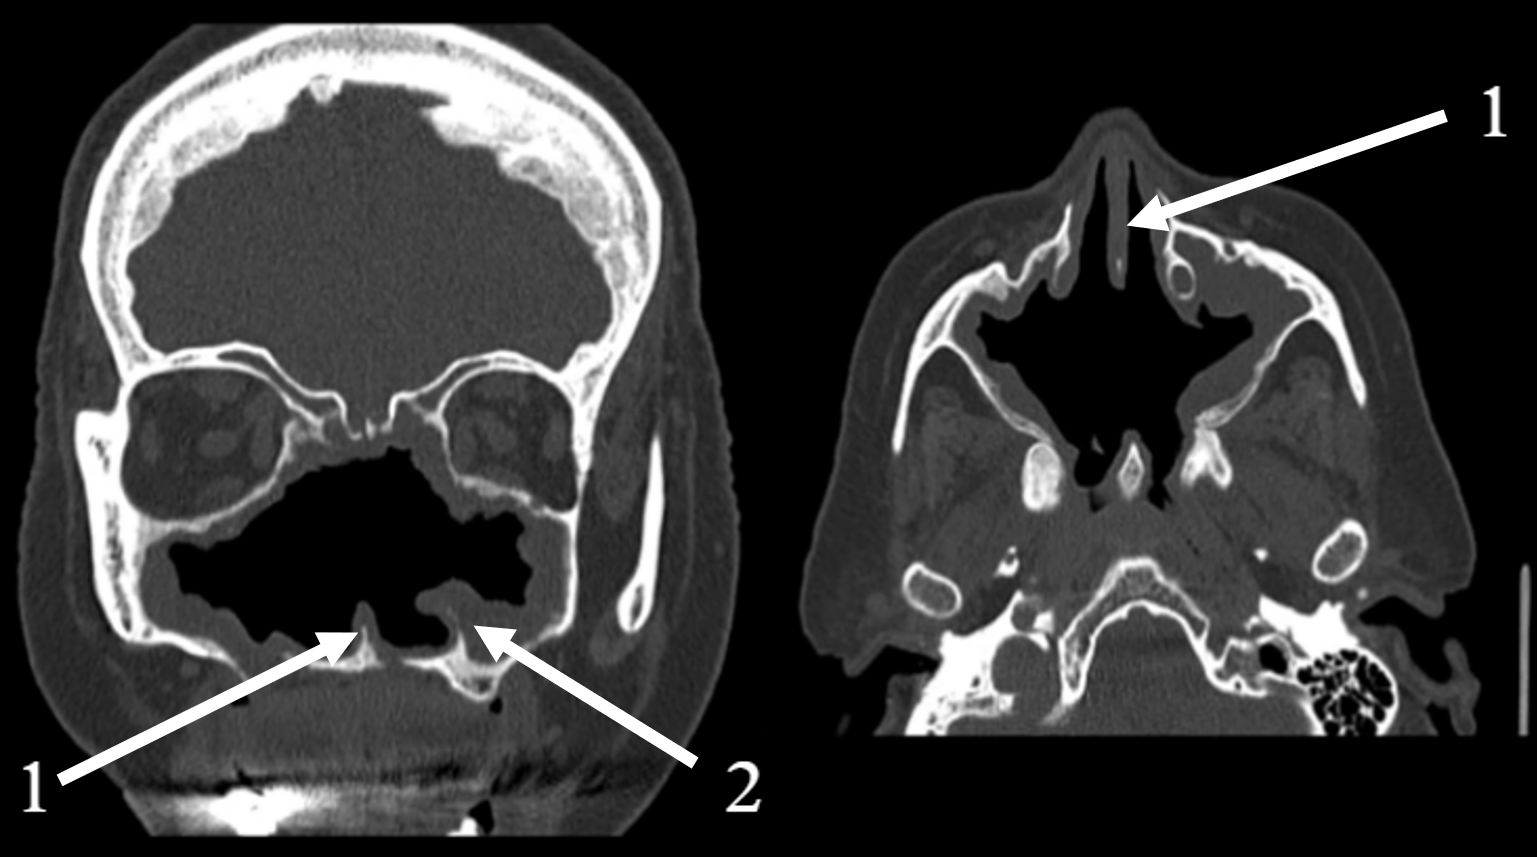

| Late September 2022 | Disease progression | CT scan reveals an “osteolytic process”. A major Polysinusotomy with necrosectomy is performed under general anesthesia, involving extensive removal of necrotic bone and tissue. The second histopathology report confirms the findings of necrotic tissue and bone fragments, with no evidence of fungal invasion or granylomatosis. |

| 2024 | Secondary atrophic rhinitis | Endoscopy, CT scan. Treatment initiation. 3-month follow-up. |